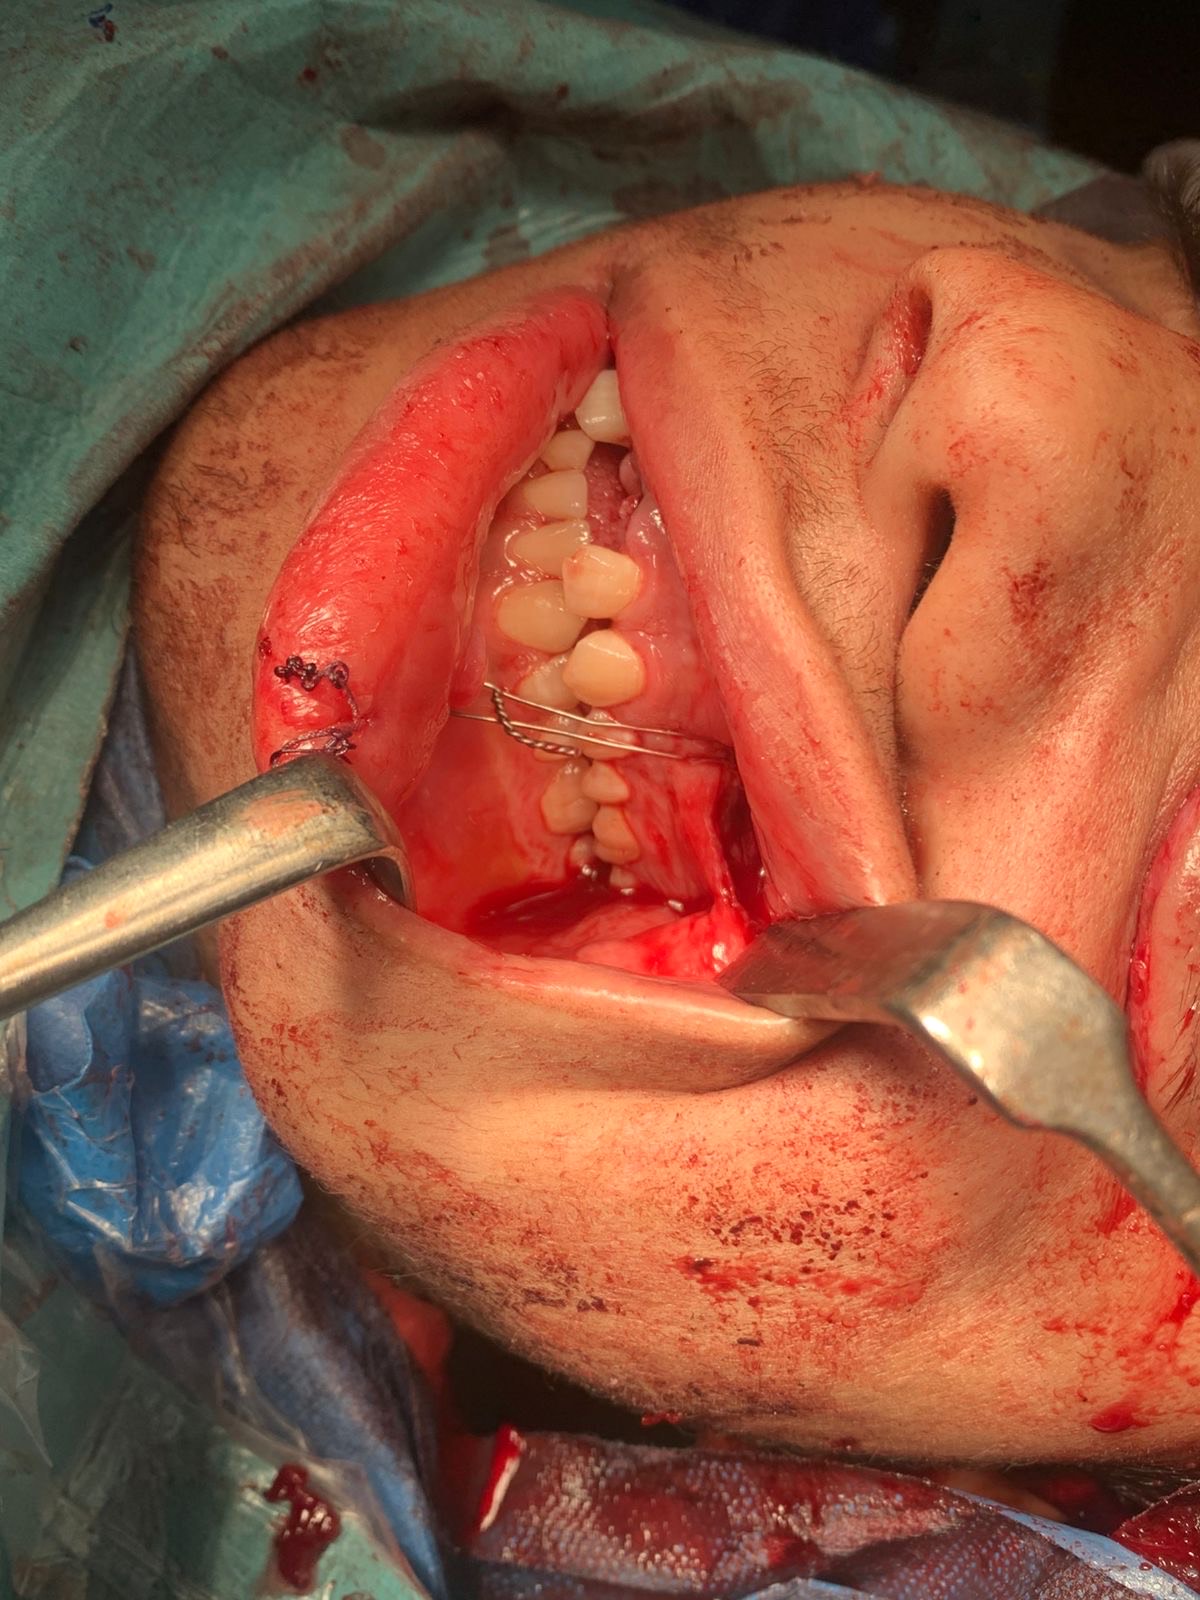

وبعد استقرار الحالة، جرى تحضير المريض لعملية دقيقة لإصلاح عظام الجمجمة والفك، حيث قام فريق جراحة الوجه والفكين برد وتثبيت محجر العين اليسرى وعظام الوجه باستخدام شرائح عالية الدقة، مع استعادة بصمة الأسنان وإعادة انغلاق الفم بشكل طبيعي، إلى جانب ترميم وإصلاح الجفن العلوي للعين اليسرى باستخدام شرائح موضعية، مع الحفاظ على المظهر الجمالي للوجه.